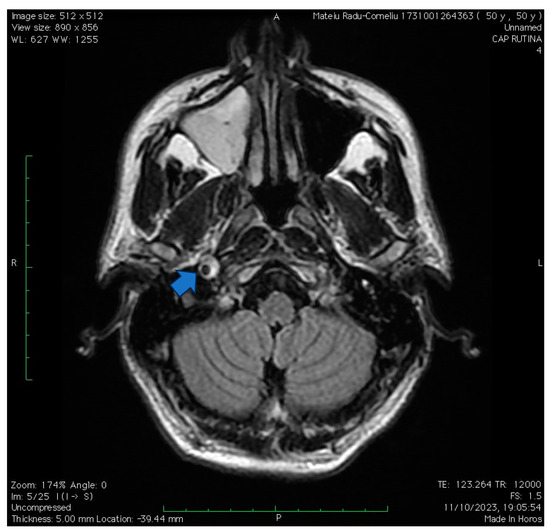

Figure 5. The case of a 50-year-old hypertensive and smoker male complaining of a weeklong anterior cervical pain and soreness following low-intensity physical effort. Upon clinical evaluation, the patient presented a right-sided Horner’s syndrome without other neurological signs. An angioCT exam and native CT scan were first performed, showing a unilateral mild right carotid artery narrowing in the immediate vicinity of the petrosal part of the temporal bone (corresponding to the proximal C3 segment of the carotid artery). A subsequent native MRI sign was performed and managed to highlight an intramural hematoma at the same level corresponding to the crescent sign (visualized using FLAIR sequence in this case- as pointed by the arrow). The ultrasonographic exam was non-remarkable. Anticoagulant therapy, as well as antiplatelet therapy, was initiated with slight improvement in regard to Horner’s syndrome upon discharge. Upon discharge, the patient received antiplatelet monotherapy. At a one-month follow-up, the patient remains oligosymptomatic, with a mild right-sided syndrome with normal pupillary function.